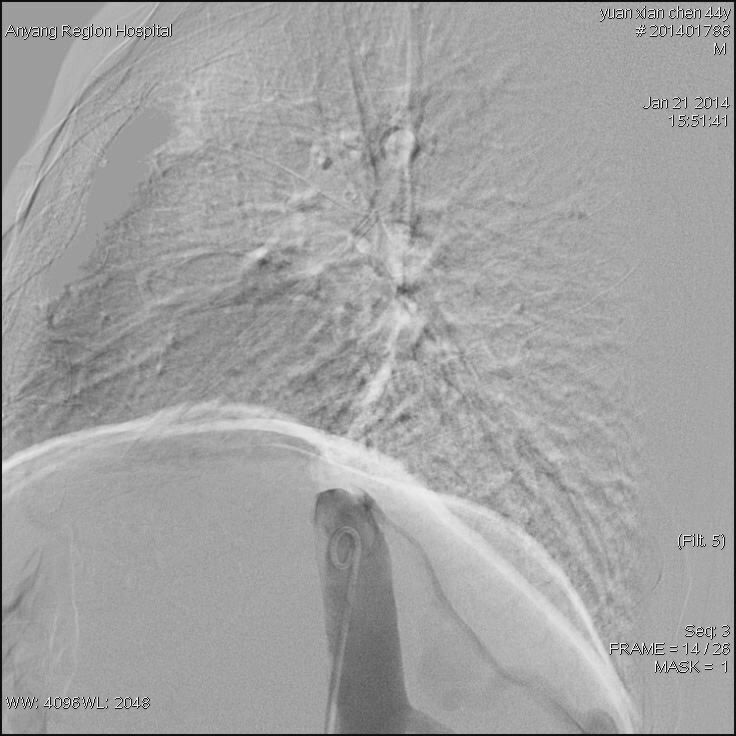

接受治疗的是一位44岁男性患者,该患者常年消化不良,身体异常瘦弱,肝脾肿大,双下肢静脉曲张合并腹壁静脉曲张,经核磁影像检查,诊断为布加综合征,考虑为下腔静脉肝后段膜性闭塞病变。我院介入科主任高毅组织科室医务人员认真研究患者病情,并详细制定出多种介入开通方案。1月21日,为患者进行了介入治疗。手术中,经穿刺股静脉与颈内静脉双向造影后,进一步明确了该患者为膜性闭塞。采用破膜针开通闭塞段,引入加硬导丝,交换引入较大球囊扩张后,患者下腔静脉瞬间畅通,下腔静脉压力明显下降,下肢静脉及腹壁静脉曲张立即消失,六小时后患者即下床活动,困扰患者多年的头晕等症状也随之消失。